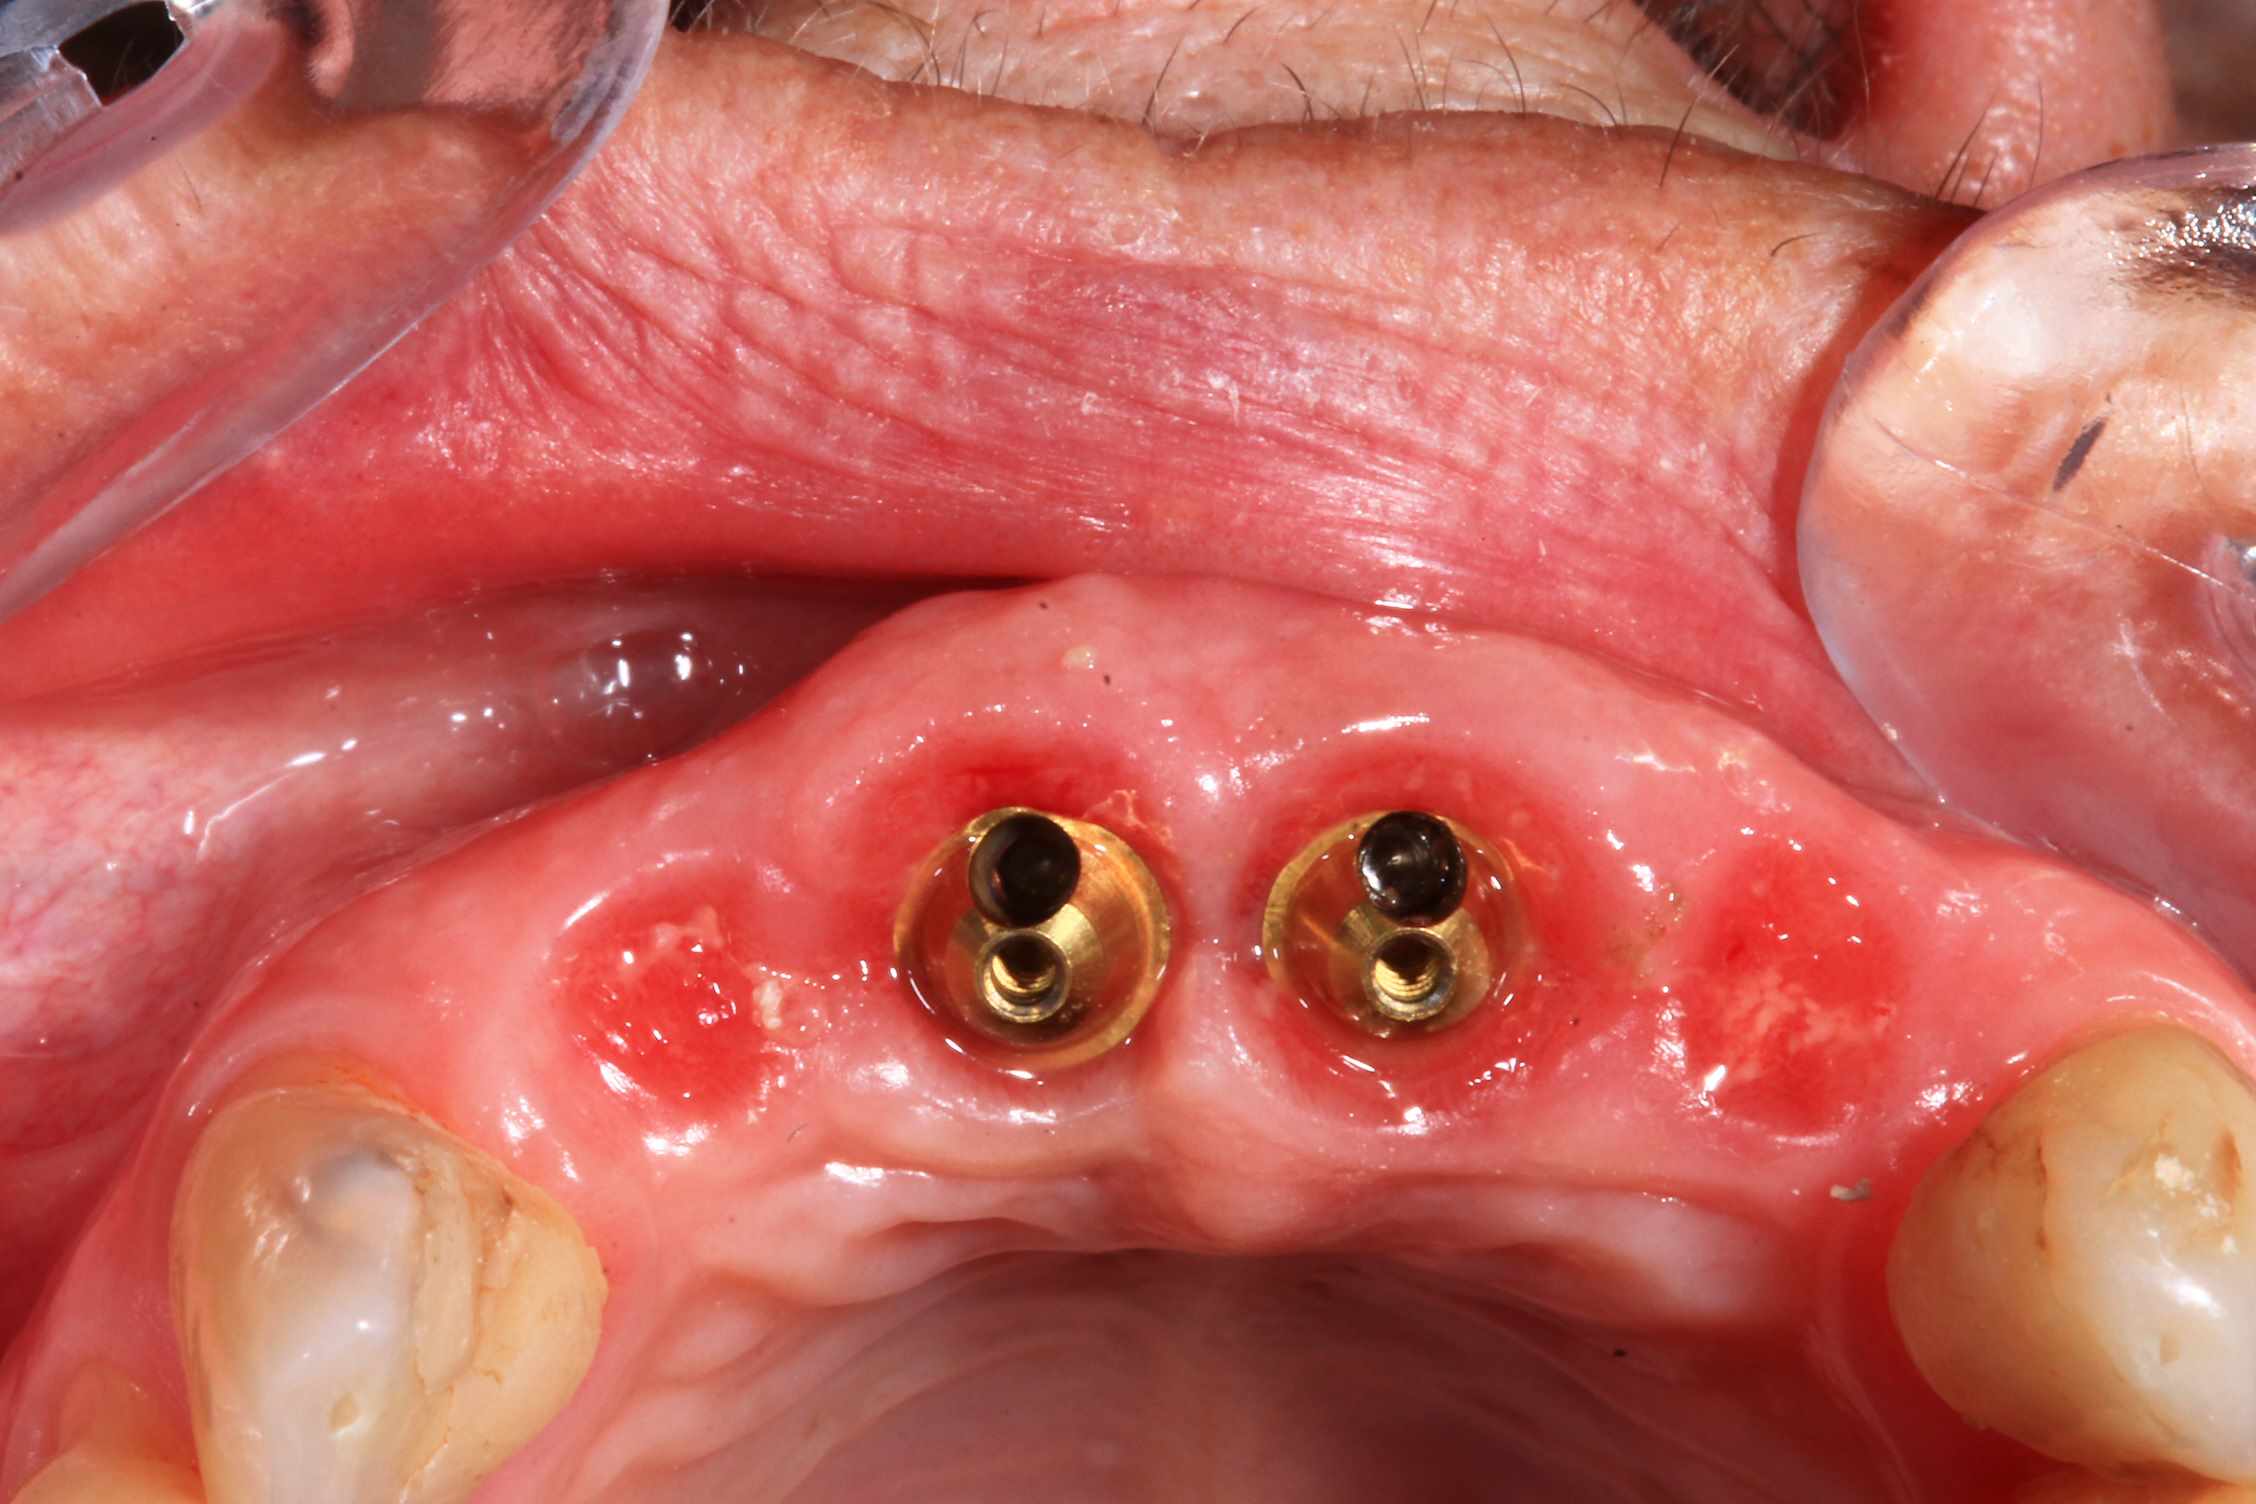

Chir : extraction, implant flapless et pose du bridge imprimé Flexera rosenscrew.

Oo2hlrfz7899rhfapzhptk1dqg77 - Eugenol

57n0uy1188a85maq093dyeqfkqlh - Eugenol

Ujfw7wykxh3fhbwxszqf740ci3rt - Eugenol

S7tplsv5ffydeo8n22bhttsnmndc - Eugenol